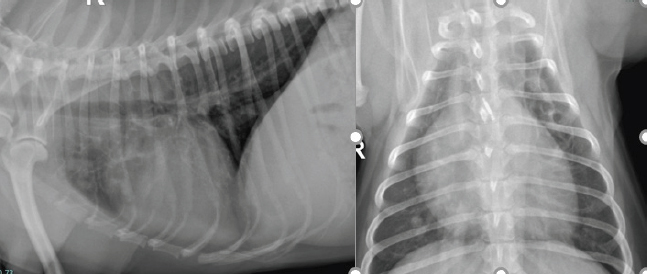

Serum biochemistry was unremarkable. Hematology revealed marked eosinophilia (7.9 × 109/l; reference range 0.06–1.23/l), moderate basophilia (0.27 × 109/l; reference range 0.00–0.1 × 109/l) and moderate elevation of platelets (PLT) (561 K/µl; reference range 148–484 K/µl) (Table 1). Thoracic radiography revealed a large soft tissue opacity in the left cranial lung lobe and mild generalized bronchiolar pattern (Fig. 1). There were no signs of pleural effusion or enlargement or tortuosity of pulmonary vessels. A mild interstitial pattern was noted in the caudal left lung lobe. An antigen heartworm test (Snap 4DX IDDEXX Laboratories) was negative (Table 1), and fecal analysis was negative for parasites too.

Fig. 1. Left lateral and dorsoventral thoracic radiograph reveals a mass in the left cranial dorsal lung field.